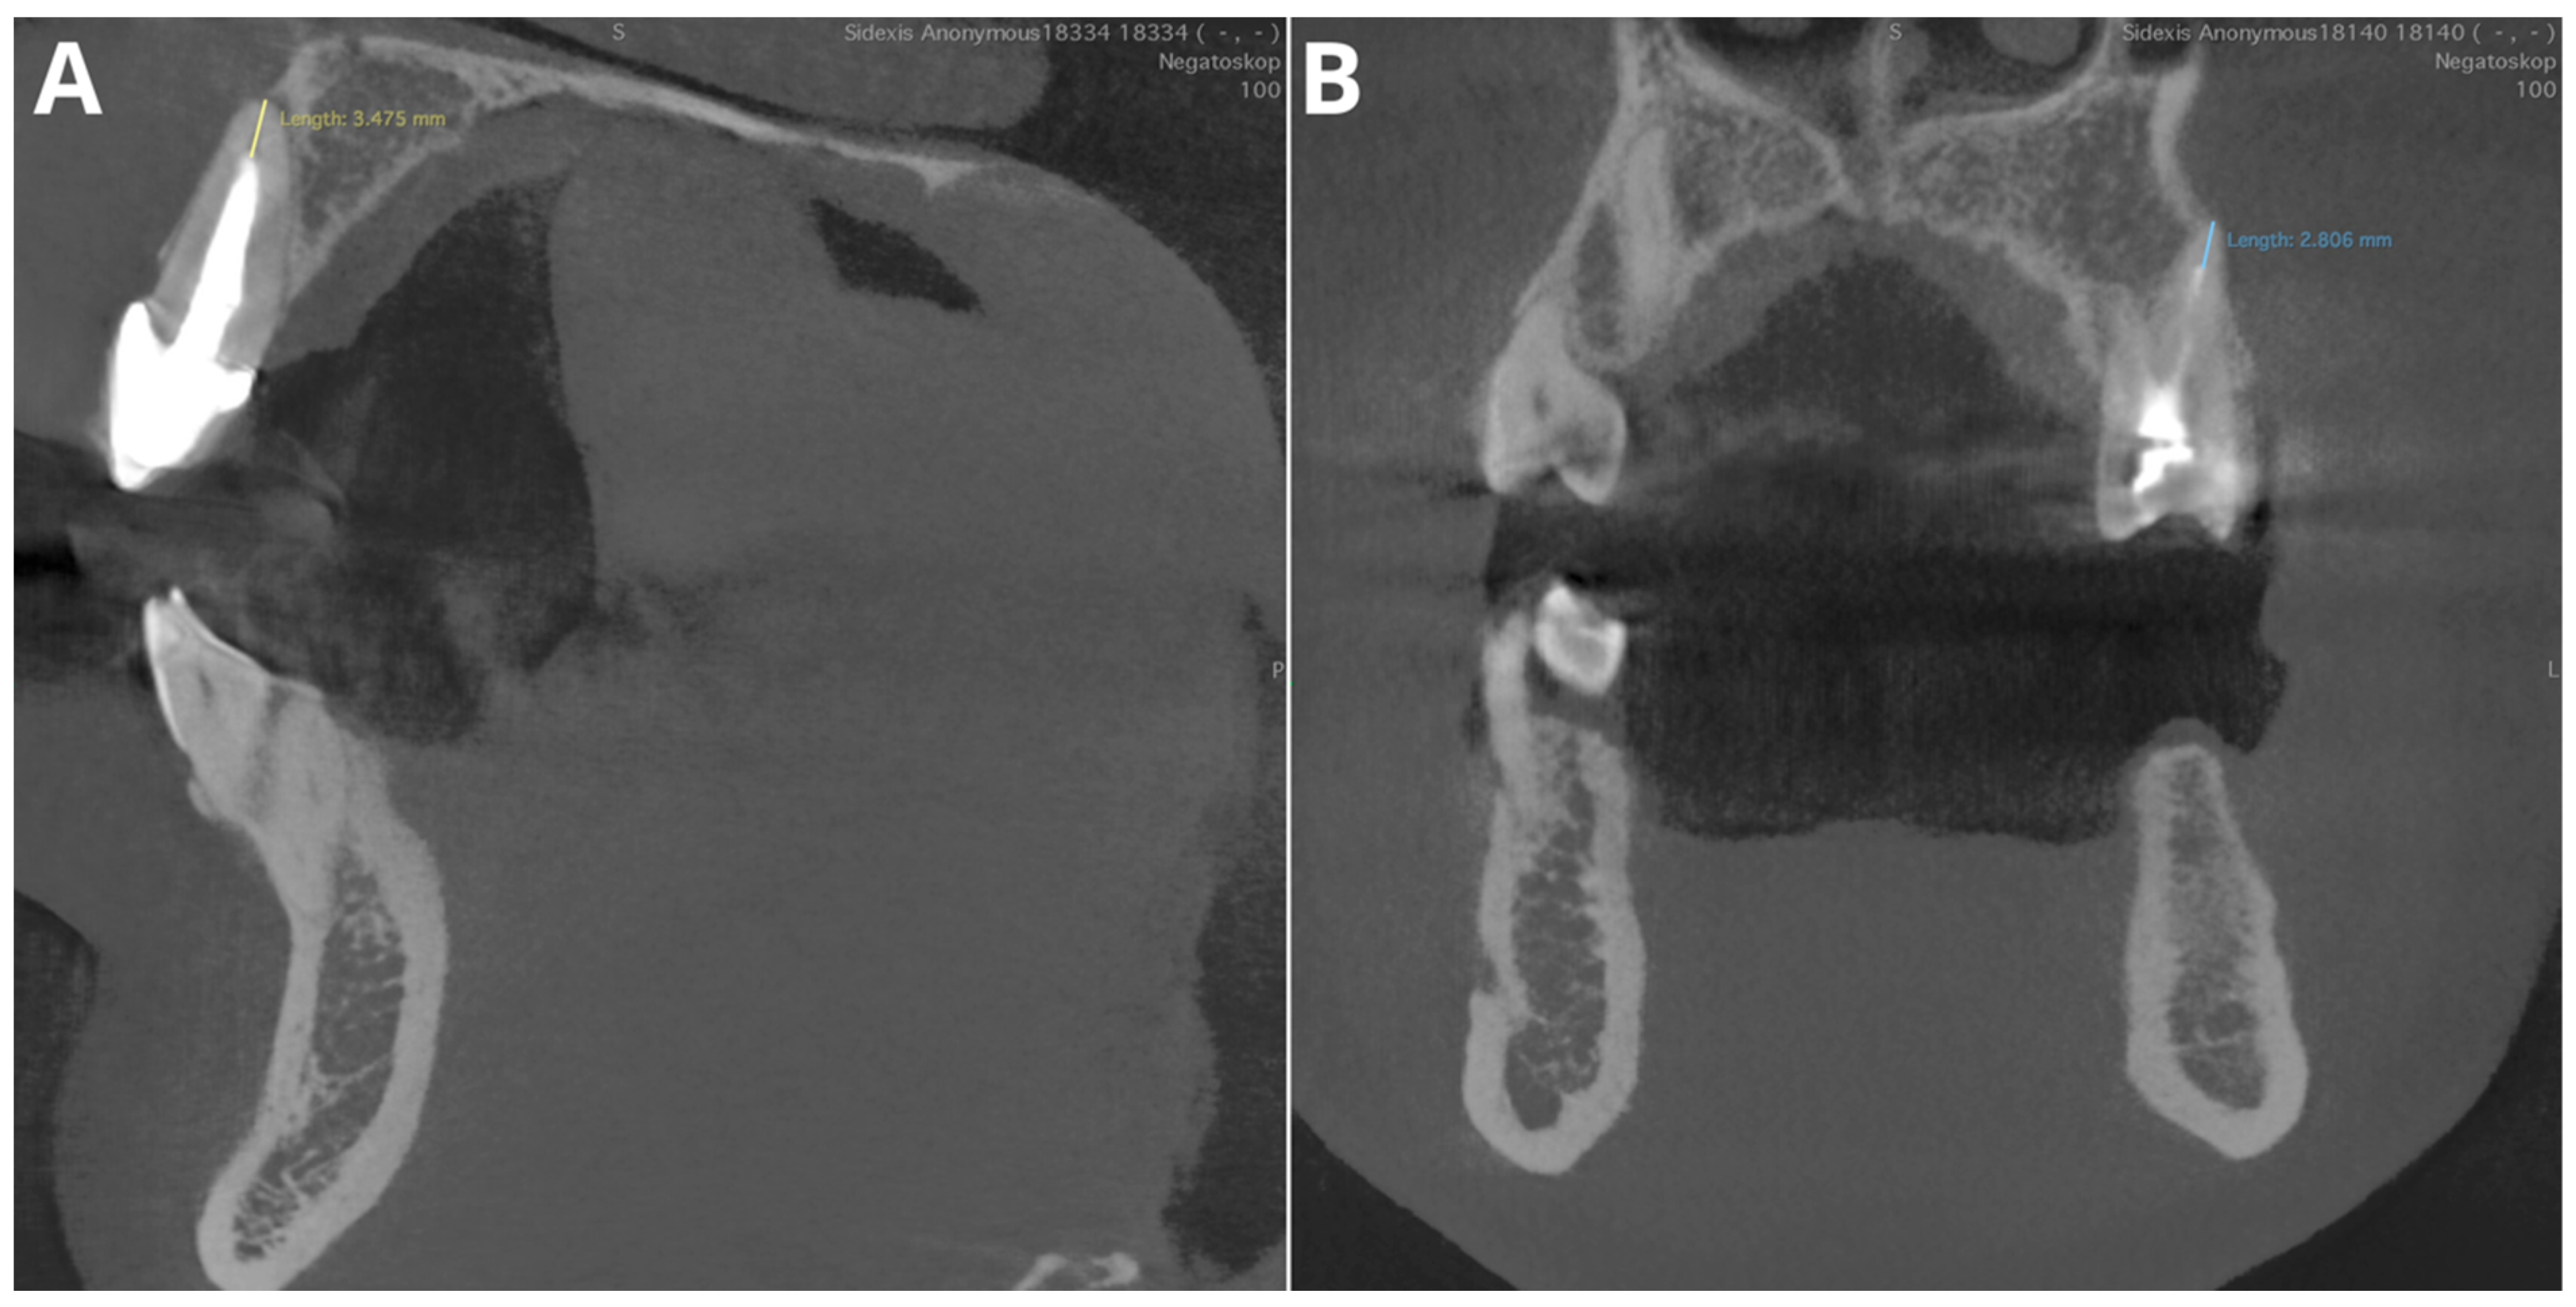

Figure 4.

Two of the false negative short-filling diagnoses. (A)—tooth 12, filling 3.5 mm from the apex; (B)—tooth 47, filling 2.8 mm from the apex.